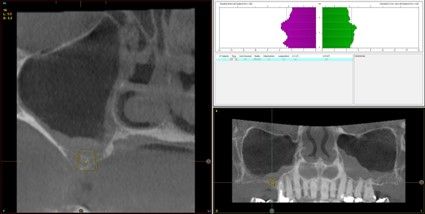

Resultados. Fueron reclutados 13 pacientes en los que se insertaron 30 implantes. Una vez insertados y cargados los implantes, la altura media final fue de 9,68 mm (+/- 2,66), lo que supone una ganancia promedio de 5 mm. A los 10 años, se observó una disminución media de la altura ósea ganada en los implantes en conjunto de 0, 29 mm (+/- 0,77). La media de la pérdida ósea mesial fue de 0,73 mm (+/- 0,75 mm) y la media de la pérdida ósea distal fue de 0,98 mm (+/- 1,2 mm). La supervivencia fue del 100%.

Results.Thirteen patients were recruited and 30 implants were inserted. Once the implants were inserted and loaded, the mean final height was 9.68 mm (+/- 2.66), which represents an average gain of 5 mm. At 10 years, there was a mean decrease in the overall bone height gain of the implants of 0.29 mm (+/- 0.77). The mean mesial bone loss was 0.73 mm (+/- 0.75 mm) and the mean distal bone loss was 0.98 mm (+/- 1.2 mm). Survival was 100%.

Los senos tratados con la técnica de elevación transcrestal sin material de relleno muestran un incremento de entre 2,5 mm12,13 hasta 4.4 mm14,15 en la altura ósea lograda sobre el ápice y una supervivencia de los implantes que se sitúa entre un 94 y un 100%16-17. En este trabajo se presenta un estudio retrospectivo donde se ha evaluado la inserción de implantes extracortos (5,5 y 6,5 mm) en zonas posteriores maxilares mediante la técnica de elevación de seno transcrestal con la fresa de ataque frontal sin la utilización de material de injerto, con un tiempo de seguimiento de 10 años para poder objetivar el comportamiento de los implantes a largo plazo y de la técnica empleada.